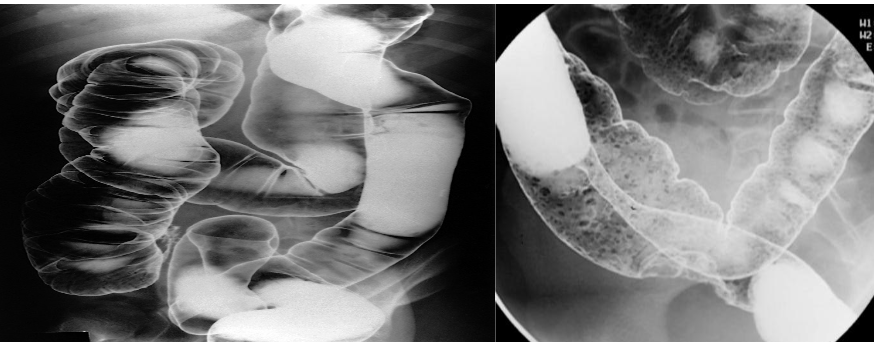

Enema double contrast which is barium & air (+ve Vs –ve)

- Double contrast - if air & fluid are present

- Single contrast - Mainly fluid